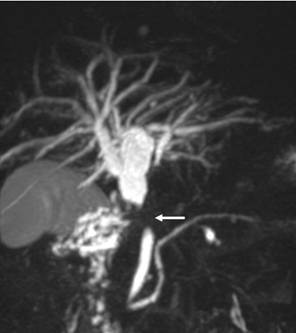

У %) больных при поступлении выявляли осложнения, сопутствующие механической желтухе (табл.2). Наиболее часто диагностировали печеночно-почечную недостаточность (15,79%) у пациентов с длительно существующей билиарной гипертензией и высокими цифрами билирубина, сопровождающуюся гемокоагуляционными расстройствами и энцефалопатией. Сопутствующий механической желтухе холангит, который диагностирован у,53%) больных, рассматривали как патологическое состояние, проявляющееся местным инфекционным воспалением желчных путей и системной воспалительной реакцией (СВР) с высоким риском перехода в билиарный сепсис [5]. При длительном существовании гнойного холангита у 7 (2,83%) пациентов выявлены холангиогенные абсцессы печени. Главной причиной их развития явились рубцовые стриктуры желчных протоков (Рис. 3) у 3 и длительно существующий холедохолитиаз (Рис. 4) у 4 пациентов. Одним из наиболее опасных осложнений механической желтухи, требующих экстренных хирургических манипуляций, считаем билиарный панкреатит, выявленный у,74%) пациентов, причиной развития которого являлся ущемленный камень БДС и спазм или стеноз сфинктера Одди (Рис. 5). При опухолях БДС и стойком нарушении оттока желчи билиарный панкреатит наблюдали лишь в 2 случаях (Рис. 6). Наиболее частыми признаками билиарного панкреатита были: боль, наличие интоксикационного синдрома с быстрым развитием гемодинамических расстройств. Желтуха при билиарном панкреатите носила, как правило, смешанный характер. [6,17].

Рис. 3 МРХПГ. Желчная гипертензия. Рубцовая стриктура проксимального отдела общего желчного протока.